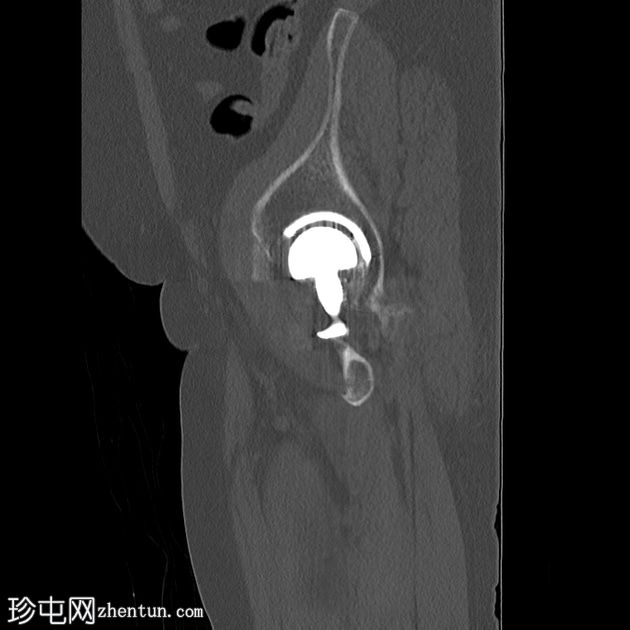

2.png

侧位片

双侧全髋关节置换术假体完整,无松动迹象。

左侧股骨大转子下区外侧皮质中断,侧位片显示最佳,提示假体周围骨折。